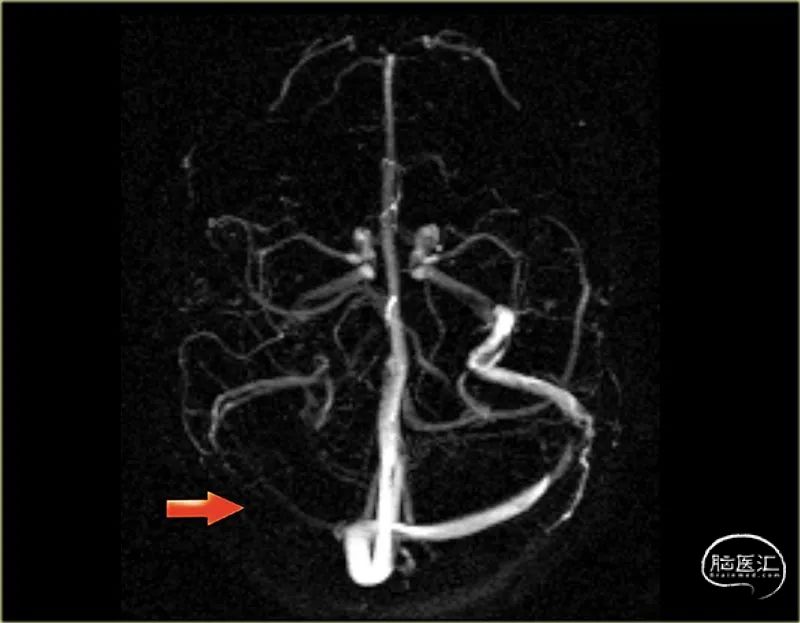

●下图 相位对比血管造影的横断MIP图像。

右横窦和颈静脉由于血栓形成而无信号。

下图为正常对比增强MR静脉造影的侧位和斜位MIP图像。

注意Trolard(红色箭头)和Labbe(蓝色箭头)的突出静脉。

一位静脉血栓形成患者的左侧图像,有血栓形成上矢状窦(红色箭头),直窦(蓝色箭头)和横向和乙状窦(黄色箭头)。